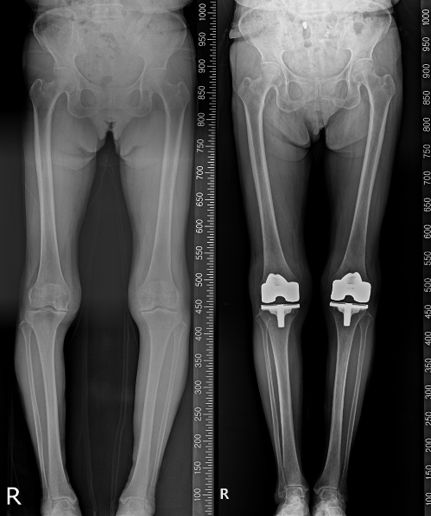

[CBC뉴스] 퇴행성 관절염은 관절을 보호하는 연골이 점차 닳아 없어지면서 통증과 변형을 유발하는 퇴행성 질환이다. 주로 무릎 관절에서 많이 발생하며, 초기에는 계단을 오르내릴 때 통증이나 뻣뻣함으로 시작해 점차 보행이 불편해지는 경우가 있다. 증상이 진행되면 통증으로 인해 걷기, 앉았다 일어서기, 장시간 외출 등 일상 활동에 제약이 생길 수 있으며, 삶의 질 전반에 영향을 줄 수도 있다. 특히 약물치료나 주사치료로 증상 조절이 충분하지 않은 경우에는 의료진 판단에 따라 인공관절 수술이 고려될 수 있다.

이러한 가운데 인공관절 수술 과정에서 정확도와 환자 만족도를 높이기 위한 다양한 시도가 이어지는 가운데, AI(인공지능) 기반 환자 맞춤형 수술 플랫폼 '니비게이트(KNEEVIGATE)'를 활용한 인공관절 치환술도 하나의 방법으로 활용되고 있다. 니비게이트는 수술 전 환자의 MRI 및 영상 데이터를 기반으로 무릎 관절의 정렬, 뼈의 형태, 변형 정도 등을 분석해 수술 계획 수립에 참고할 수 있도록 돕는 플랫폼이다.

니비게이트 인공관절 수술의 특징 중 하나는 PSI(Patient Specific Instrument, 환자 맞춤형 수술 가이드)를 적용한다는 점이다. PSI는 환자 개인의 해부학적 특성을 반영해 제작된 절삭 가이드로, 수술 중 뼈를 절삭하는 위치와 각도 설정 과정에서 참고 자료로 활용된다. 이를 통해 획일적인 방식에서 벗어나 환자별 특성을 고려한 수술을 진행하는 데 도움이 될 수 있다.

니비게이트 플랫폼을 활용한 인공관절 수술은 환자별 무릎 정렬과 관절 구조를 반영한 수술 계획 수립, 절삭 과정에서의 오차를 줄이기 위한 접근, 연부조직 손상 최소화, 수술 결과의 예측 가능성 제고 등과 같은 측면에서 의미가 있다는 설명이다. 다만 수술 결과와 회복 정도는 환자 상태와 의료진 판단, 수술 방법 등에 따라 달라질 수 있어 개별 평가가 필요하다.

연세사랑병원 고용곤 병원장은 "퇴행성 관절염 환자는 같은 진단명이라도 관절 변형의 정도와 뼈의 형태가 모두 다르기 때문에 환자 맞춤형 수술이 중요하다"며 "니비게이트 플랫폼과 PSI를 활용한 인공관절 수술은 환자의 해부학적 특성을 반영해 수술 계획을 세우는 데 참고가 될 수 있다"고 말했다.